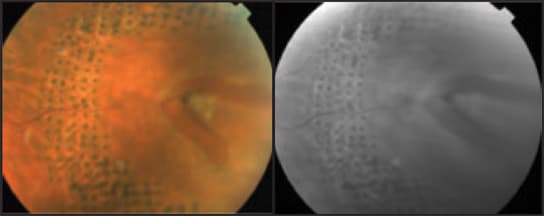

Figure 1. Color and red free photographs demonstrate the improvement in a peripheral retinal break 1 month after treatment with PASCAL laser irradiation.

Reaching the retinal periphery is easy with the PASCAL Photocoagulator, which is not necessarily the case with all of the conventional lasers available today. Not much distortion of the laser spots occurs in the peripheral retina, even when a 5 × 5 pattern or 3 × 3 pattern array is used. The typical power for peripheral treatments is 300-700 mW. I often use a spot size of 200 μm (at the slit lamp) and either the 3 × 3 or 2 × 2 pattern array to make a nice contour around the lesions.